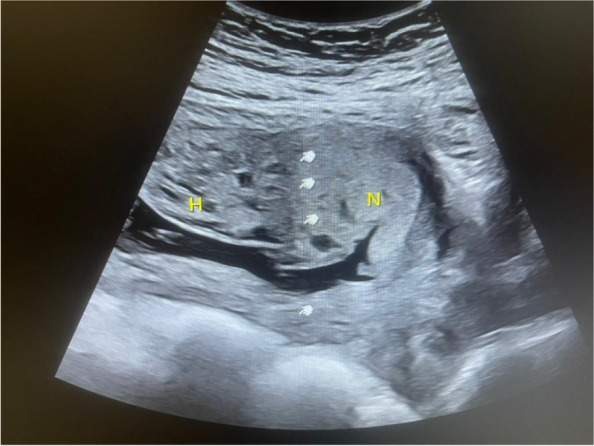

Multiple placental cysts are a common finding in obstetric ultrasound imaging. Although they have benign differential diagnoses, such as hydropic degeneration of the placenta or placental mesenchymal dysplasia, it's important to consider significant pathologies, such as benign gestational trophoblastic disease or hydatidiform mole. A challenging issue in obstetrics is pregnancies with a placenta that has a bipartite texture. This means that one side of the placenta is normal, but the other side is full of cystic formations, and only one fetus is visualized. The main critical concern is the presence of a molar pregnancy because of its catastrophic consequences. Here, we report a rare case in which the gravid uterus had a normal diploid fetus but had a bipartite placenta, which was triploid in the hydropic part, revealing a unique genetic pattern.